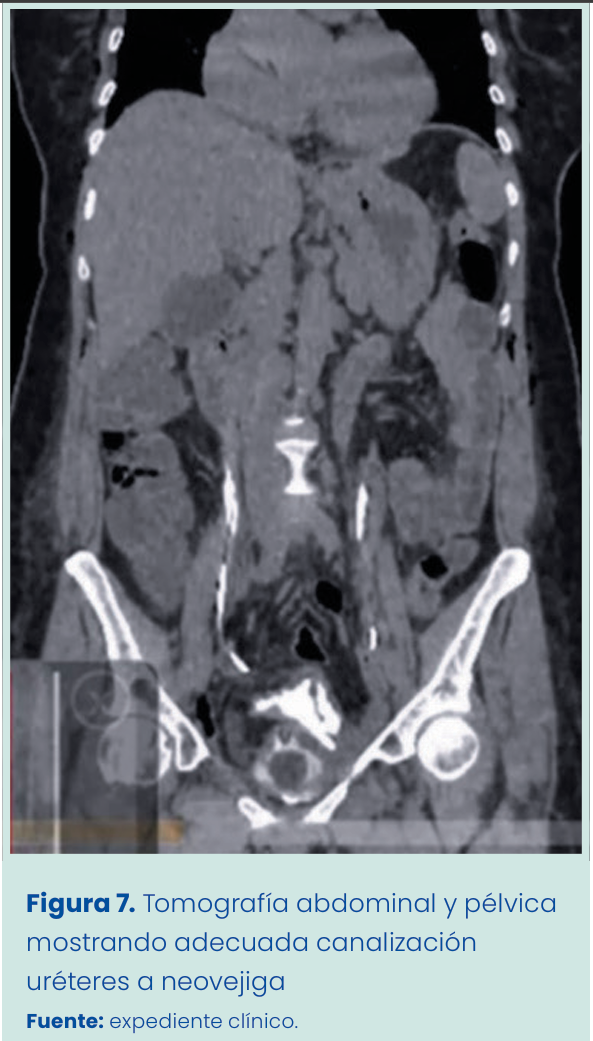

Debido a la buena evolución de la paciente y su buen estado metabólico, al tercer día es trasladada a sala común cuando comienza a presentar evacuaciones pastosas y se progresa a dieta blanda. Se realiza estudio de tomografía abdominal y pélvica con efecto urográfico que muestra correcta canalización de ureteres a neovejiga sin datos de obstrucción intestinal, sin extravasación de orina por neovejiga y sin colecciones intraabdominales (Figura 7)

Figura 1. Grapadora lineal vascular aplicada en bloque al pedículo renal.